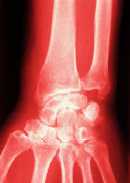

Bei rheumatischen Erkrankungen unterscheidet man - abhängig von der Ursache - zwei große Gruppen: die entzündlichen rheumatischen Erkrankungen und die degenerativen rheumatischen Erkrankungen.

Die rheumatoide Arthritis ist typischer Vertreter der entzündlichen rheumatischen Erkrankungen. Arthrosen dagegen gehören zu den degenerativen Erkrankungen, die hauptsächlich durch Abnutzung und Verschleiß in den Gelenken entstehen.